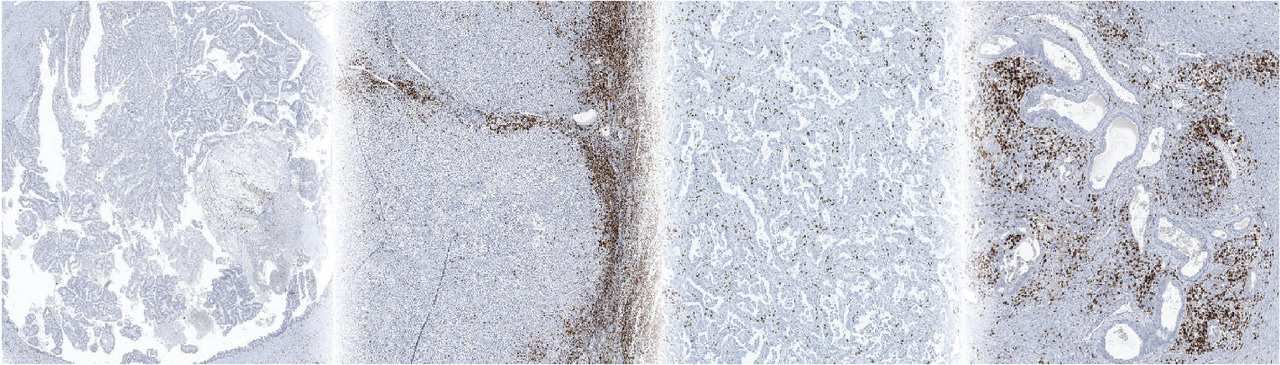

The 4-steps protocol from patients to bench. (From left to right) A member of our team (Marjolein de Bruijn) on stand-by to collect tumor tissue at Pathology. Right after at the laboratory, she dissects the tumor piece into small fragments of 1-2 mm3. Then the processed material is frozen and subsequently used in our culture system.

Now we could use the platform to dissect the observed immunological responses. By perturbing T cell activation and signaling pathways, we found that tumor-resident T cells were crucial to initiate these immunological responses and induced the secretion of multiple T cell chemoattractants in the tumor. These findings suggest a model in which PD-1 blockade may induce a local immune response in the tumor by reinvigorating tumor-resident T cells that subsequently promotes the recruitment of potentially more functional peripheral T cells, as observed in patients at later timepoints [1]. In addition, we identified baseline tumor properties associated with response or resistance to PD-1 blockade. Most interestingly and in line with earlier observations from our lab [2], we observed that the presence of a specific population of tumor-reactive T cells, so called PD-1T TILs, were highly predictive for response to PD-1 blockade. In addition, paralleling the predictive value established for clinical response [3-5], we found that the presence of tertiary lymphoid structures was also predictive for immunological response to anti-PD-1.